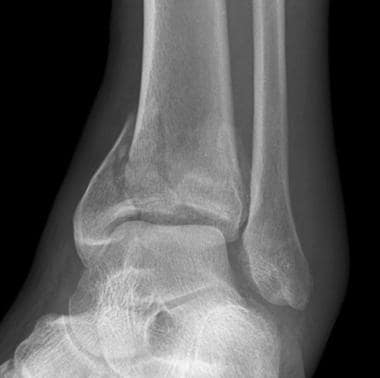

Diagnosis

Taking a thorough history of the condition will identify some of the symptoms already mentioned. Through the hands on assessment, we will be able to identify:

Pain when pressing the sole of your foot, where the fascia inserts into the heel bone

Positive Windlass test

It is also important to rule out other potential problems that may present similar to plantar heel pain, such as fat pad irritation or a nerve irritation.